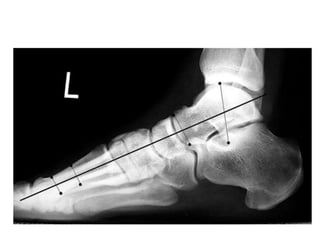

Lateral view

• The lateral talocalcaneal angle

Talocalcaneal angle

Angle between

the mid-talar

axis and calcaneal

inclination axis.

-normally measure

between 30° and 45°

-decreased in a varus

foot and increased in a

valgus hindfoot

Meary angle

• B/n long axis of the talus and the long axis of

the 1st MT

• Normally, these lines are colinear

• apex directed dorsally-cavus foot

• apex angled plantarward- valgus or flatfeet

Hibb angle

• angle between the plantar surface of the

calcaneus and the first metatarsal

• Normally Hibb angle is

greater than

150 degrees

Calcaneal pitch

• Angle between the horizontal and the plantar

surface of the calcaneus

• Important in evaluating a cavus foot or

clubfoot

• low: 10-20° - indicative of pes planus

• medium: 20-30°

• high: ≥30° - indicative of pes cavus